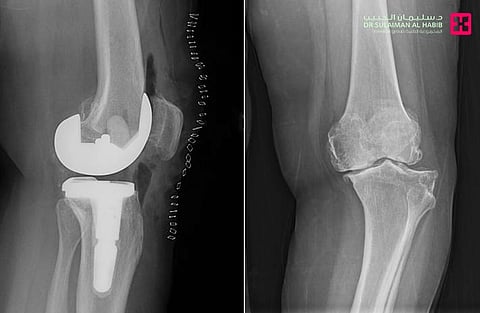

وأوضح الدكتور عبدالله الشهراني، استشاري جراحة العظام واستبدال المفاصل الصناعية ورئيس الفريق الطبي المعالج، أن المريضة حضرت وهي تشكو من آلام وتورم وتغيّر في شكل الركبة وصعوبة في الحركة. وأضاف أن الفحص السريري والفحوصات الدقيقة أظهرت وجود احتكاك حاد وتآكل في عظمتي المفصل، إضافة إلى ارتخاء شديد في الأربطة الجانبية وخلل في حركة عظمة رأس الركبة.

وبيّن الشهراني أن الفريق الطبي درس الحالة بدقة، وتوصّل إلى أن استبدال المفصل بآخر صناعي هو الخيار الأنسب، حيث أُجريت العملية باستخدام مفصل خاص بهذه الحالات وبالاستعانة بأحدث الأجهزة الطبية. واستغرقت العملية نحو 60 دقيقة، وتكللت بالنجاح، إذ تمكّنت المريضة من المشي بعد ساعات فقط من إجرائها، وغادرت المستشفى بعد أيام بحالة صحية جيدة.

وأشار الشهراني إلى أن التقنية المستخدمة تختلف عن الطرق التقليدية، إذ لا تتطلب قطع رباط العضلة الرباعية وتحافظ على الأنسجة المحيطة، مما يقلل الآلام بعد الجراحة ويُسهم في تقصير فترات التنويم والعلاج الطبيعي والتأهيل.